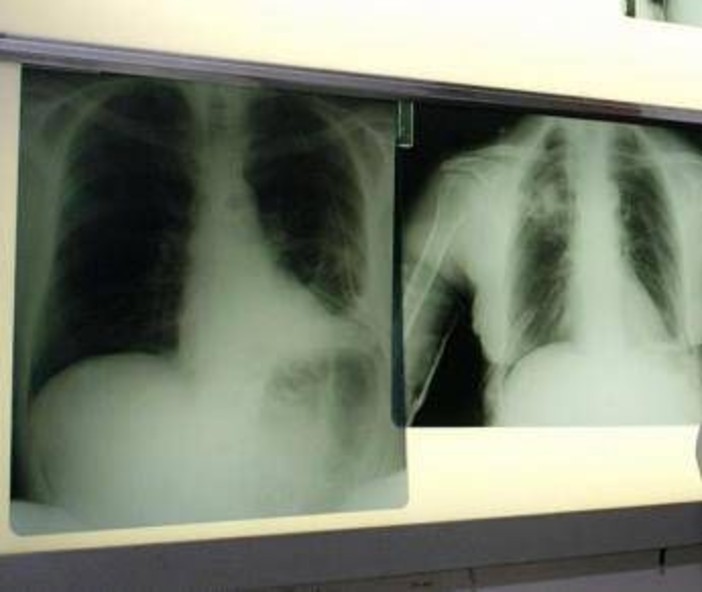

(Adnkronos) - Ogni anno circa 290mila casi di infezione respiratoria acuta negli adulti e 1.800 decessi. Sono i numeri registrati solo in Italia per il virus respiratorio sinciziale (Vrs o Rsv nella sigla inglese), che si presenta con sintomi simil-influenzali, ma può determinare complicanze respiratorie significative nei soggetti fragili come over 60, persone immunocompromesse e neonati. Un fenomeno sottovalutato e sottostimato, specialmente nella popolazione adulta e anziana: spesso, infatti, la malattia da Rsv non viene diagnosticata correttamente. La protezione dei soggetti fragili resta la priorità: in Italia si registrano infatti oltre 50mila ricoveri all'anno. Nel dettaglio si calcano circa 25mila ospedalizzazioni di bambini sotto i 5 anni di età legate alle complicanze come bronchiolite e polmoniti, e circa 26mila negli over 60. Sul fronte della prevenzione, sono oggi disponibili strumenti sicuri ed efficaci come la vaccinazione e l'immunoprofilassi; nonostante queste opportunità, però, l'Rsv non è ancora incluso nel Piano nazionale di prevenzione vaccinale (Pnpv).

Il virus respiratorio sinciziale colpisce in modo diverso nelle differenti fasce d'età. L'Rsv "è un virus ubiquitario che colpisce praticamente tutti i bambini entro i 2 anni di vita, con possibili reinfezioni nel corso della prima infanzia e financo in età adulta - illustra Paolo Manzoni, professore associato di Pediatria e neonatologia, università di Torino – Se nei soggetti oltre i 2 anni di età il virus causa spesso sintomi simil-influenzali, colpendo per lo più le vie aeree superiori, al contrario una percentuale importante di pazienti con età meno di 2 anni presenta coinvolgimento delle basse vie aeree che può sfociare, nello specifico, nel quadro clinico classico conosciuto come bronchiolite e nelle sue complicanze sia immediate, sia a lungo termine". Oltre ai neonati prematuri e di età inferiore ai 6 mesi, le popolazioni a rischio di sviluppare una patologia respiratoria grave a seguito di Rsv sono le persone over 60 e quelle immunocompromesse o con patologie preesistenti come il diabete, le malattie cardiache e polmonari, nelle quali il virus può scendere alle vie respiratorie inferiori causando principalmente polmonite.